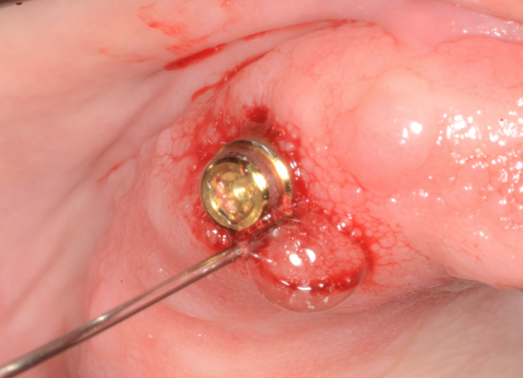

Ozone is used in peri-implantitis or where the beginning of inflammation is seen in mucositis by using a cannula (Figure 7) to blow the gas directly underneath the tissues affected. Although this has been around for more than 100 years, until recently there were few studies, likely due to the advent of antibiotic resistance to antimicrobials. However, one that studied the influence of gaseous ozone in peri-implantitis reported that a 24-second treatment around areas of the inflammation can sterilize and eliminate the microorganisms Strep sanguinis and Porphyromonas gingivalis without affecting the osteoblasts and the tissue cells.28

Cannula used to administer ozone subgingival therapy for treatment of peri-implant mucositis.

Figure 7